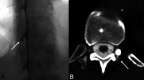

Materials and methods: A retrospective review was completed of patients with suspected spontaneous intracranial hypotension who underwent brain MR imaging followed by digital subtraction myelography with same-day CT myelography. Patients with and without leaks found on digital subtraction myelography were included. MRIs were assessed for numerous reported stigmata of spontaneous intracranial hypotension and were compared between cohorts.

Results: One hundred seventy-four patients were included; 113 (64.9%) were women (average age, 52.0 [SD, 14.3] years). A CSF leak was found in 98 (56.3%) patients, nearly all of which (93.9%) were CSF-venous fistulas. Diffuse dural enhancement, internal auditory canals dural enhancement, non-Chiari cerebellar descent, pituitary engorgement, brain sag, dural venous sinus engorgement, and decreased suprasellar cistern size were associated with a CSF leak. A probabilistic scoring system was made in which a single point value was assigned to each of those findings: 0-2 considered low probability and ≥3 considered intermediate-to-high probability of a CSF leak.